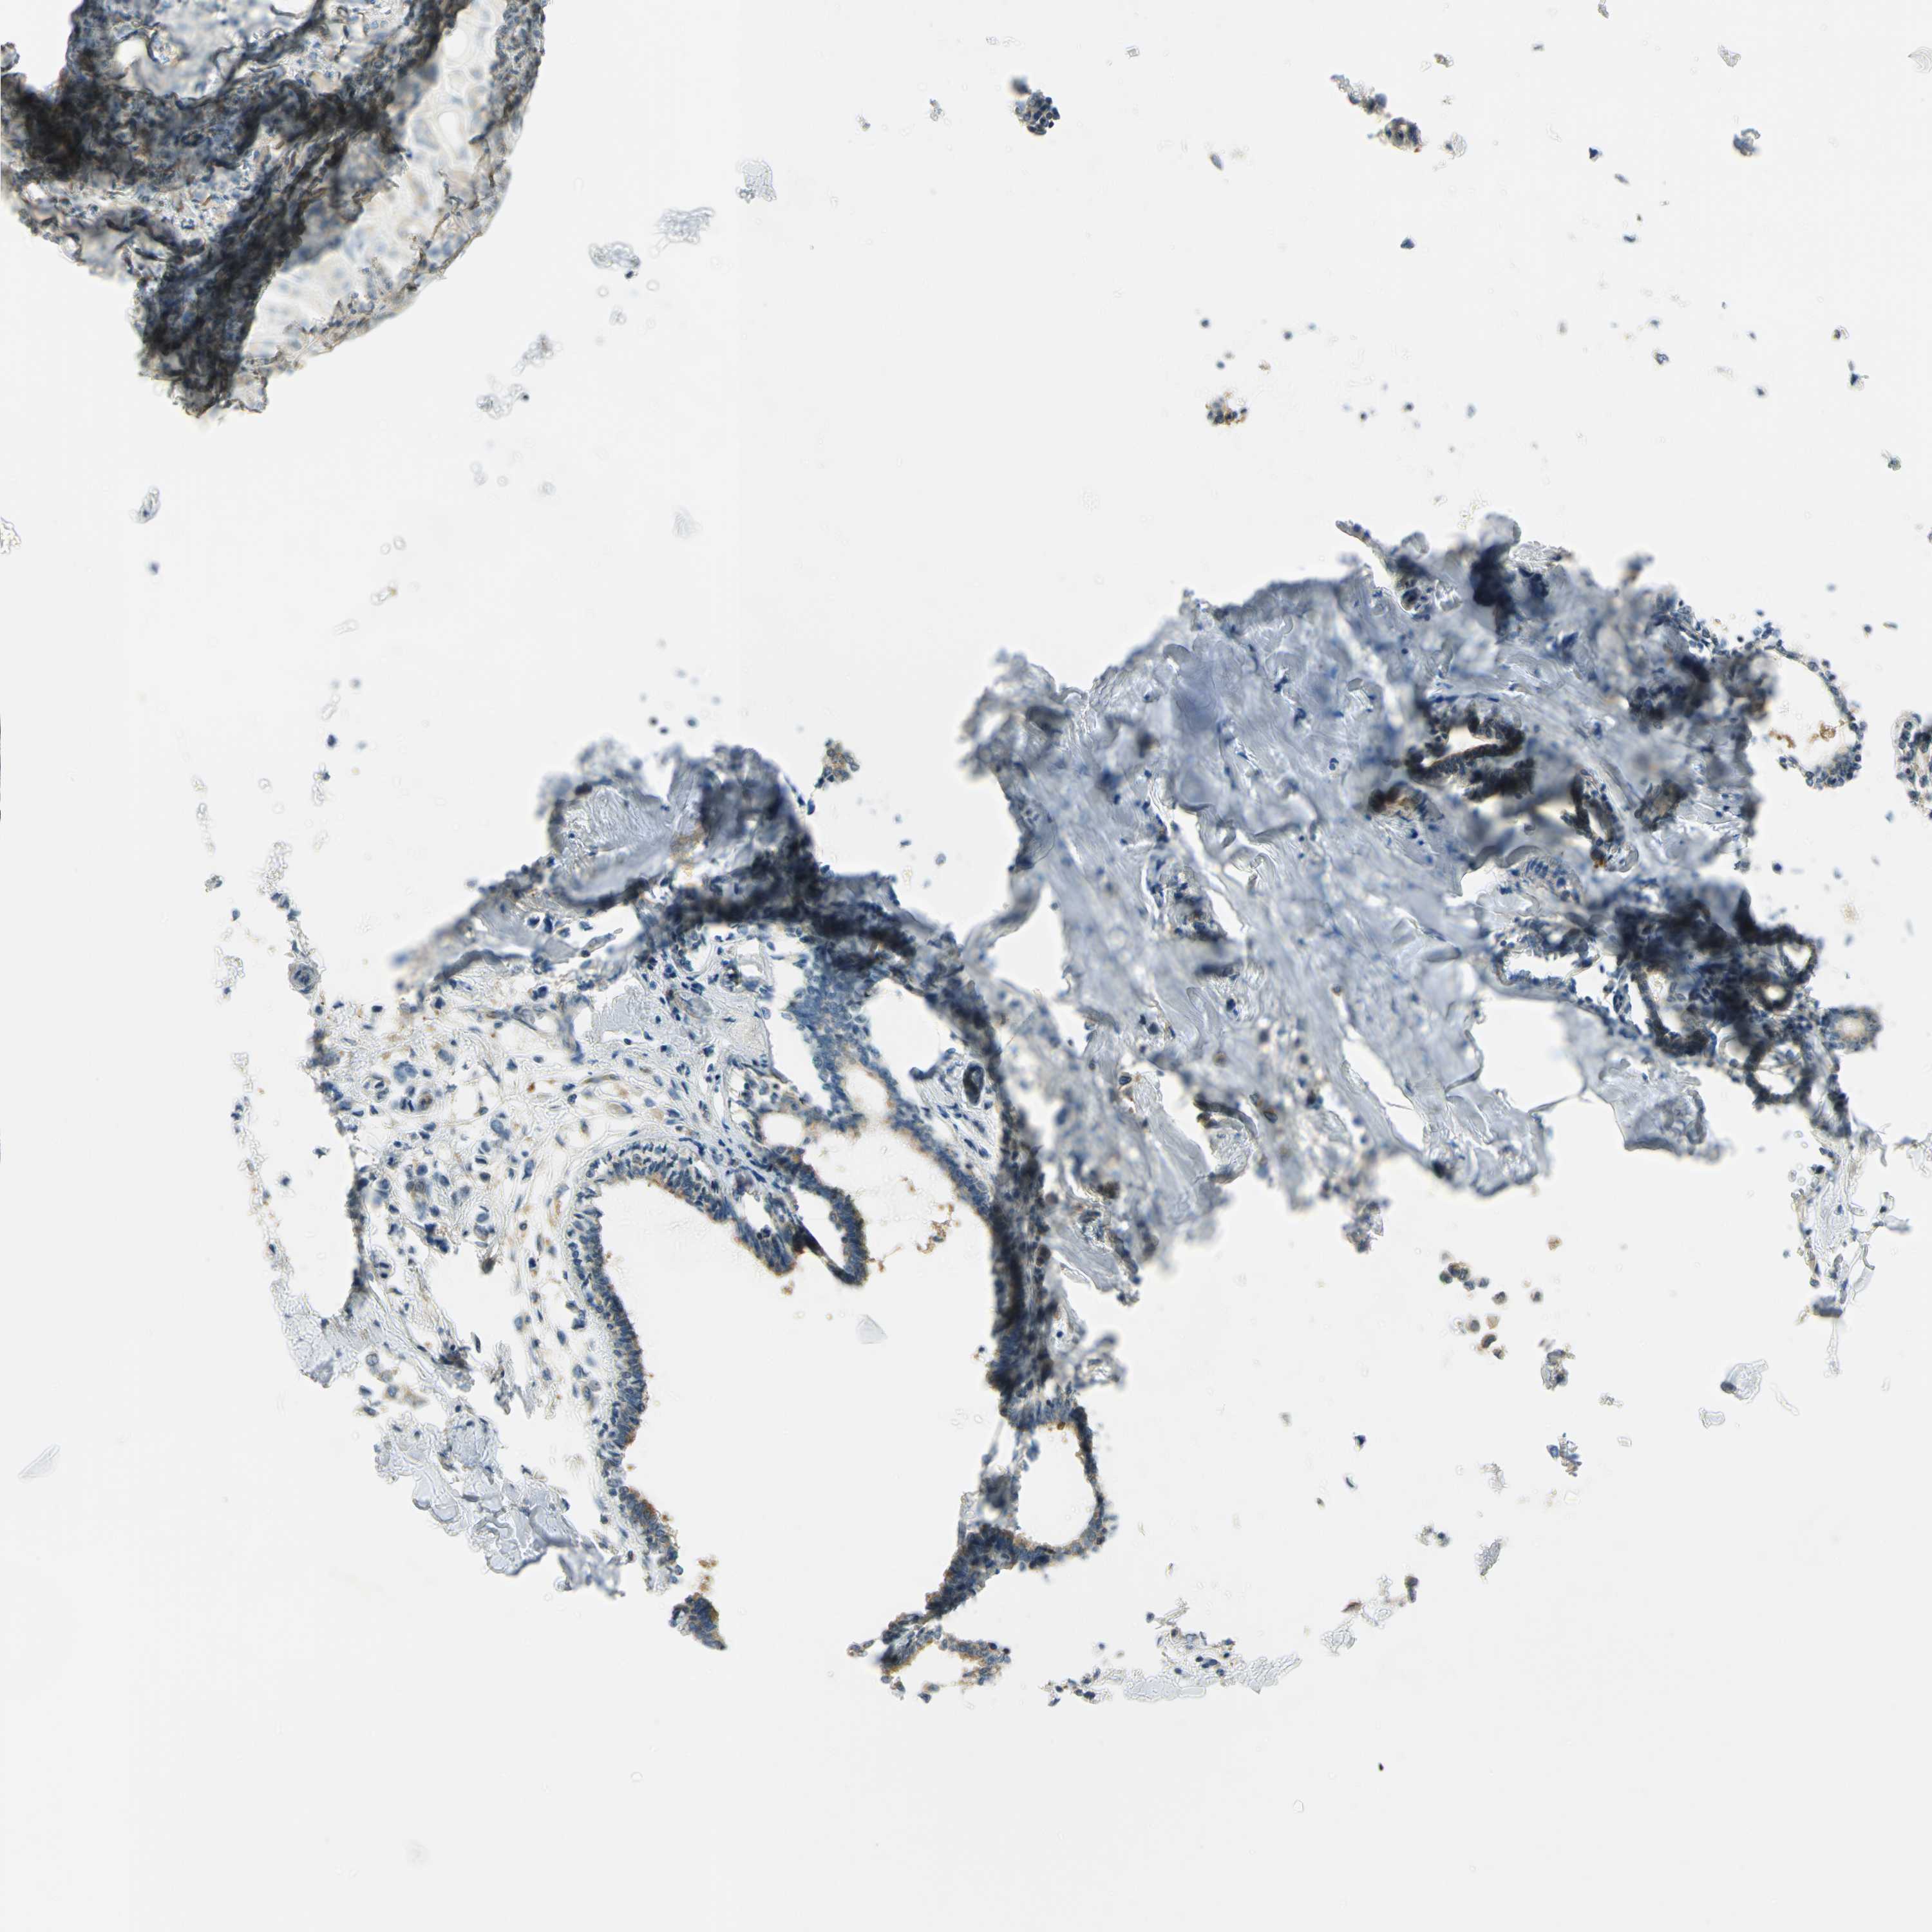

BRCA TCGA BRCA VALIDATION PROTEIN EXPRESSION

ANTIBODIES

AND

VALIDATION